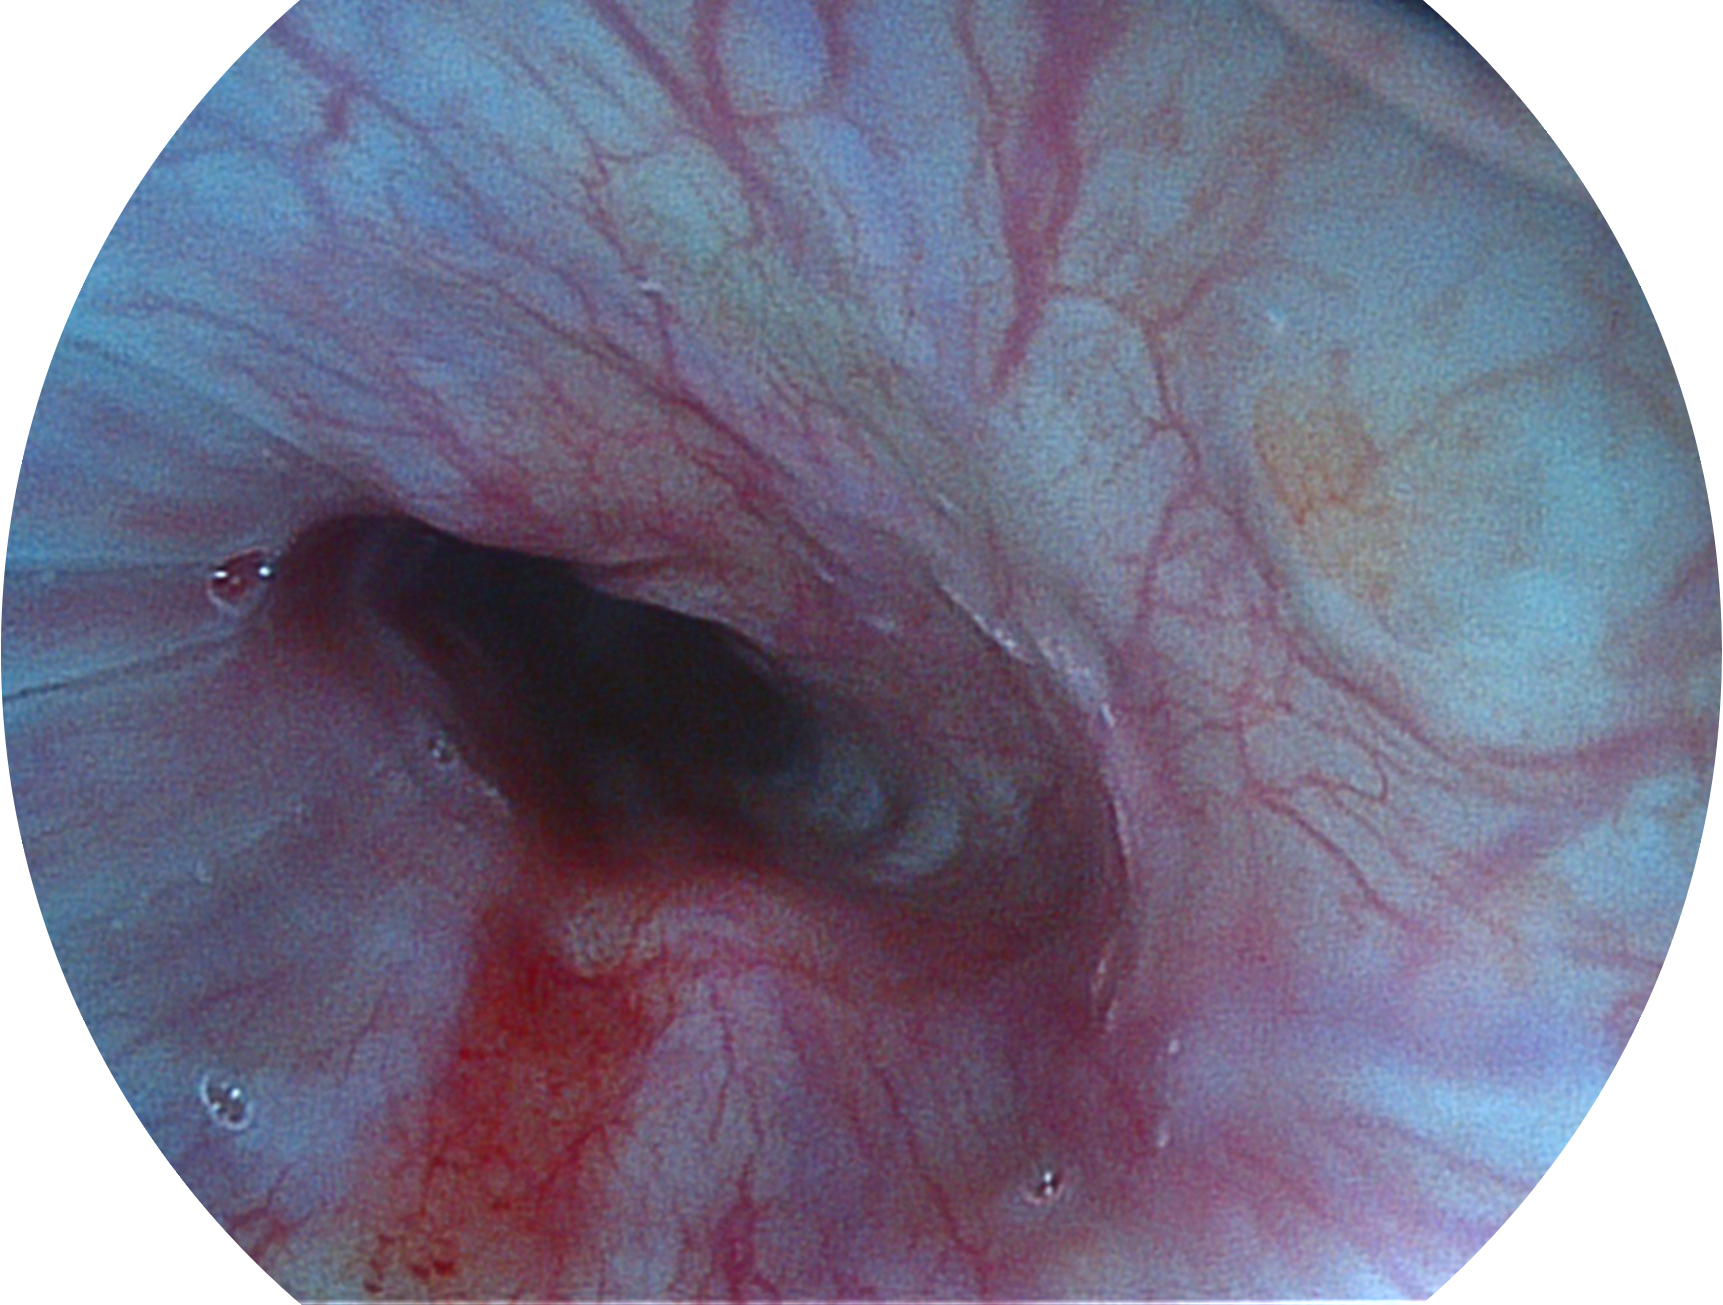

milan米兰新开发的内镜染色技术,主要是基于多波长LED 光源的开发,VLS-55Q 四波长LED 光源是由四个不同颜色的LED光按照相应照明模式所规定的特定发光比例进行合束后形成,合束后形成的照明光的光谱由红光、绿光、蓝光及蓝紫光这四个不同的波段范围构成。具有更高光谱自由度,通过光谱比例的控制,实现了聚谱成像技术,英文全称为“Spectral Focused Imaging, SFI”,缩写为“SFI”和光电复合染色成像技术,英文全称为“Versatile Intelligent Staining Technology, VIST”,缩写为“VIST”。